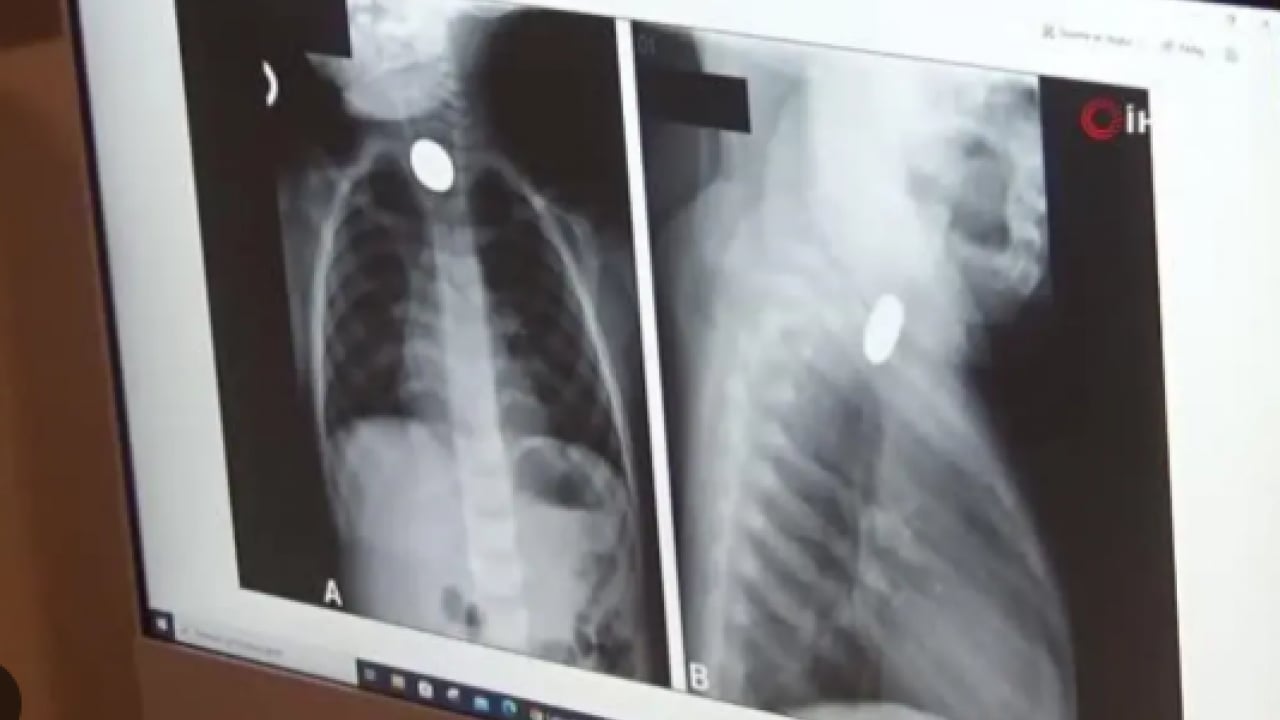

BULANTI VE KUSMA ŞİKAYETİYLE HASTANELİK OLDU Peker’in mıknatıs yuttuğundan habersiz olan ailesi, karın ağrısı, bulantı ve kusma şikayetleri üzerine kızlarını Nusaybin Devlet Hastanesi’ne götürdü. Yapılan röntgende yabancı cisim tespit edilmesi üzerine Peker, Mardin Eğitim ve Araştırma Hastanesi’ne sevk edildi.

"PARÇACIKLI OYUNCAKLARDAN VE PİLLERDEN UZAK TUTUN" Ufak parçacıklı oyuncakların özellikle 6 yaşından küçük çocuklara verilmemesi gerektiği konusunda aileleri uyaran Op. Dr. Mürsel Haspulat, “Basit görünen bir oyuncak çocuğumuzu ölümle burun buruna getirdi. Bu tür mıknatıslar bağırsaklarda birleşerek hayati risk oluşturabiliyor. Aileler özellikle kış aylarında çocuklarını küçük ve parçalı oyuncaklardan, pillerden ve sert gıdalardan uzak tutmalı. 4 yaşındaki Eda, karın ağrısı ve kusma şikayetiyle geldi. Normalde basit bir şekilde apandisit ya da bağırsak düğümlenmesi diye düşünebildiğimiz bir vakaydı.

Ama sonrasında röntgenlerini çekip hızlıca ameliyata almamız gereken bir durumla karşı karşıya kaldık. Çünkü ailenin de fark etmediği şekilde 2-3 hafta içinde tane tane mıknatıs parçalarını yutmuş ve bu mıknatıs parçaları bağırsakları birbirine yaklaştırarak düğümlenmesine ve delinmesine neden olup çocuğun bağırsaklarının tıkanmasına neden olmuştu. Ameliyatta öncelikli karmaşık tabloyu tek tek çözerek delinmiş bağırsak kısımlarını onardık. 3 saat boyunca uğraştık, devamında ameliyatın ortasında röntgen çektik tekrar içeride başka bir parçacık var mı diye kontrol ettik. Bir tane kalmıştı, onu da çıkartıp ameliyatı tamamladık. Fakat çok ağır bir ameliyat olduğu ve genel durumu da bozulmuş olduğu için çocuğumuz 6 gün boyunca yoğun bakımda yatmak zorunda kaldı. Yoğun bakımda 3’üncü gününde çok şükür beslenmeye başladı, daha sonra da servisi aldık. Şu anda taburcu ettik. Çok iyi ve şanslı bir vaka olarak sonuçlandı. dedi.